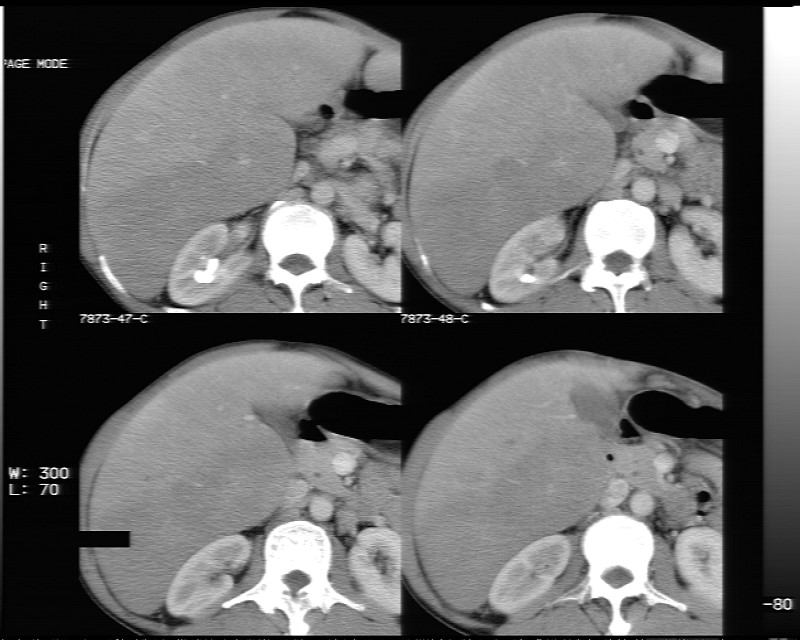

动态增强示:

支持脂肪肝【无占位性,高低密度区同期强化,平扫与强化的密度成比例】

不均匀性脂肪肝。肝脏体积稍大,不除外合并肝功能损害。

1.脂肪肝;

2.右肾结石。

不均匀性脂肪肝 。支持!右肾结石

1、不均匀脂肪肝;2、布加氏综合症(肝脏肿大,门脉纤细,下腔海绵状变性,肠系膜上静脉显著扩张)。